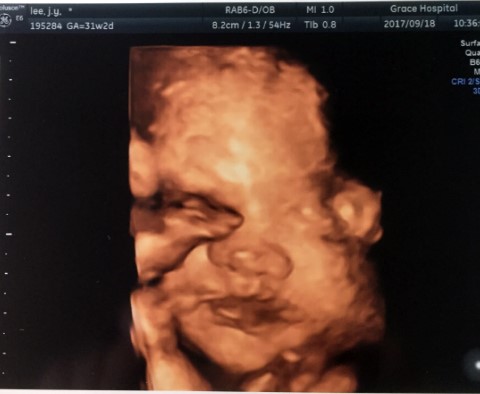

벌써 30주가 넘어가고... 이런저런 검사도 별탈없이 지나가줘서 고마운 우리기동이. 여름에 부쩍 커진 배로...